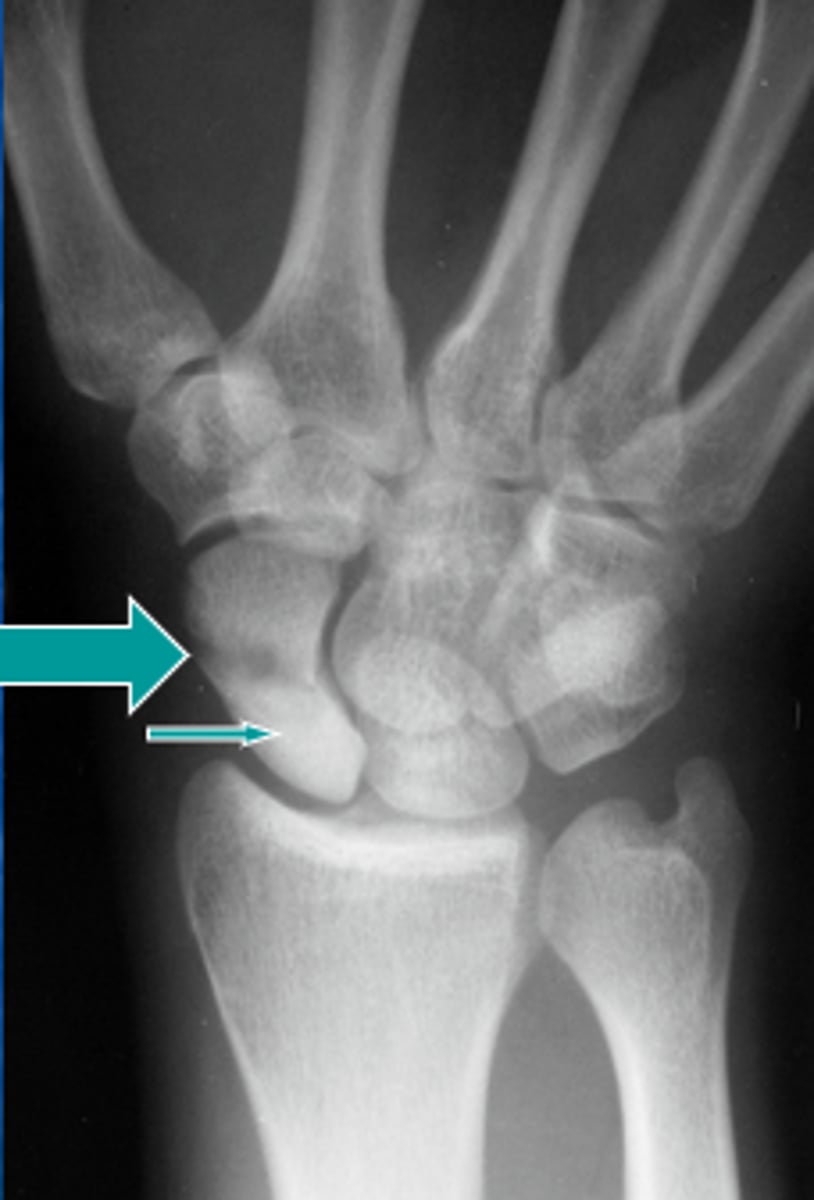

Patient presents to the ER following a fall complaining of pain in the "snuff box". Do you see any thing?

Answer

Possible AVN. Its sclerotic looking

The films were normal now what do you want to do? What other imaging could you also consider?

-Follow up in another 7-10 days with x-ray

-Could also use MRI

Here it is 3 months later

Proximal mid and distal poles are sclerotic